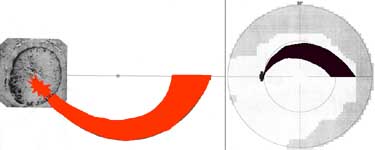

Při aplikaci křenové peroxidázy do oblasti od středu terče až k jeho okraji tato proniká do gangliových buněk v obloukovitém okrsku zasahujícím od terče až temporálně od makuly. Na perimetru tomu odpovídá arkuátní skotom v protilehlé polovině zorného pole.